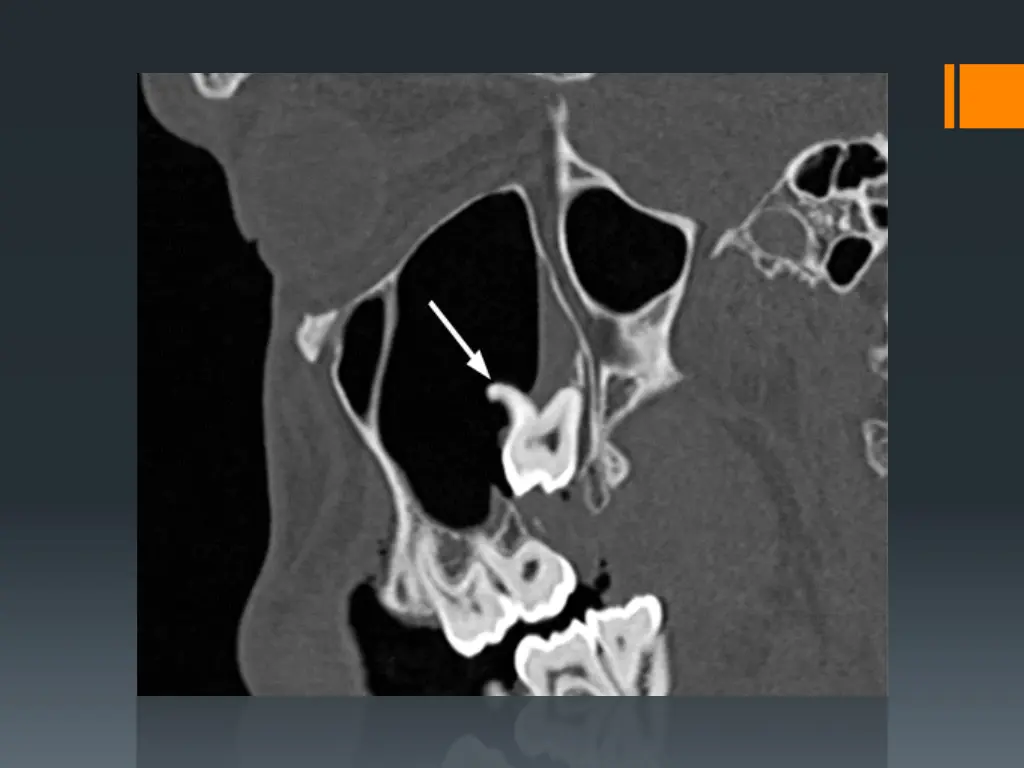

5. Displacement of a root into the soft tissue and tissue spaces and the maxillary antrum: -

During extraction especially on use of elevator, a root or piece of root may be dislodged into the soft tissue through a very thin bony plate overlying the socket and disappear buccally or lingually into the soft tissue between periosteum and bone in the vestibule, but sometimes a root or even a tooth may be displaced into the tissue spaces surrounding the jaws e.g. a retained root in the lower molar teeth may be displaced into the sublingual or submandibular space or e.g. upper third molar may displaced into the infratemporal space.

So the extraction with high force without direct vision on the retained root may lead to such complications, also retained root may be displaced into the maxillary antrum during the extraction of upper molar or sometimes premolar teeth especially palatal root of upper molar teeth. The presence of large antrum or the use of excessive force during extraction or due to pathological conditions like periapical pathology. All these factors may assist or predispose to such complication, so pre-operative radiograph and clinical evaluation may assist in the prevention of such complication.